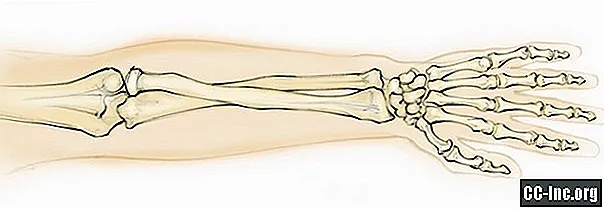

Радиоульнарный угол: строение и особенности лучевой кости